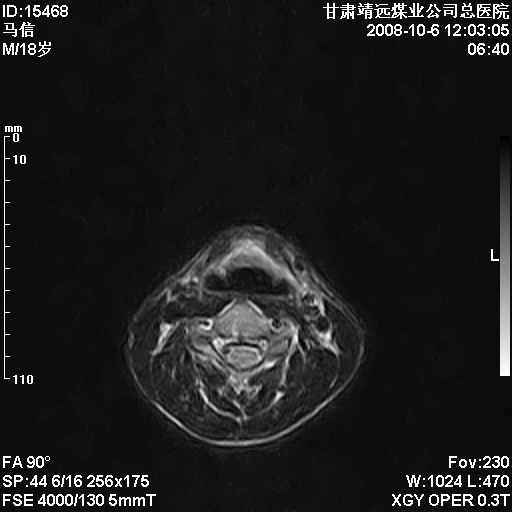

标题: MRI1827:颈椎内异常信号,是不是占位。

患者18岁,学生,在玩耍中受伤来检查,患者喜欢打篮球。颈椎内异常信号影,我们考虑占位,但是不像占位,又考虑硬膜囊的增厚,大家关建看颈椎椎管内的那个异常占位信号

脑脊液流动伪影?

后纵韧带增厚,颈2/3、3/4、4/5、5/6椎间盘变性、突出;椎体有旋转,提示椎小关节有问题;腰椎间盘变性,许莫氏结节。

是正常的脑脊液波动伪影

脑脊液流动伪影

你说的占位是伪影。在我们医院1.5t和3.0t的mr上是经常看见的。